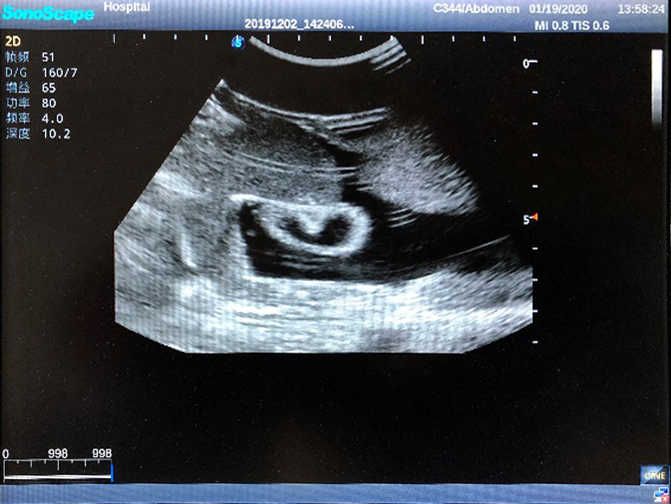

1)  Ideal for trainings like ultrasound-guided abdominocentesis with visible ascites flowing out, ultrasound-guided femoral artery & venous puncture

2)  High quality ultrasound image with clear structures like gallbladder, liver, intestines, arteries and veins etc.